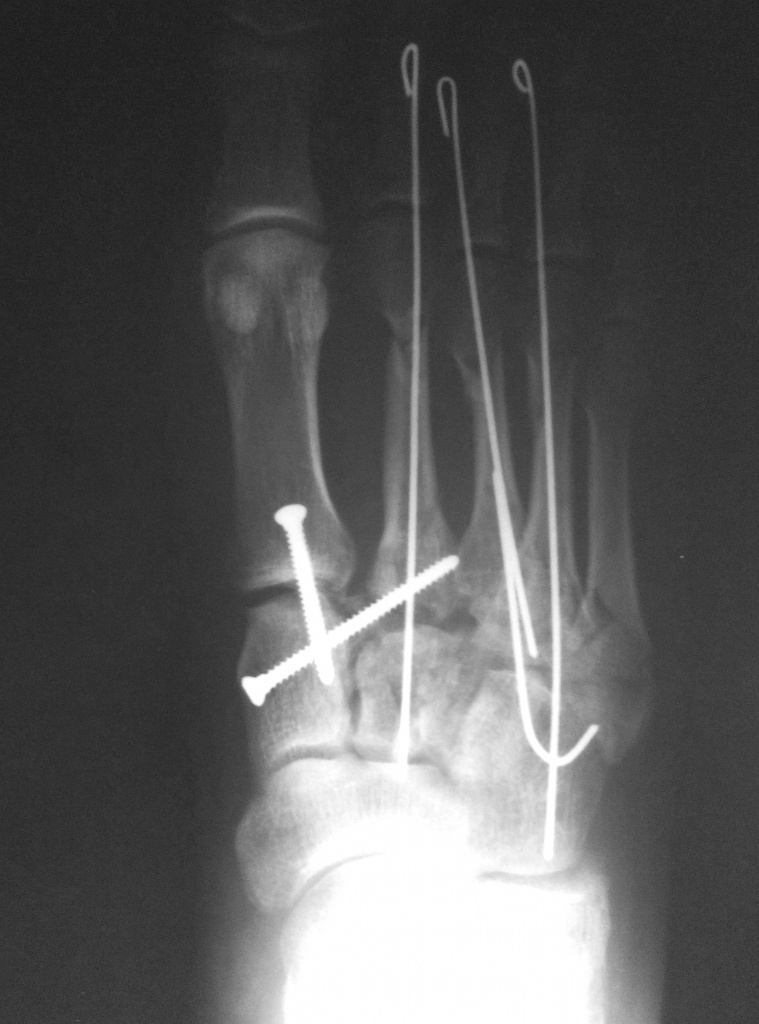

Тяжелое повреждение переднего и среднего отделов правой стопы

Рентгенограммы после реконструкции правой стопы